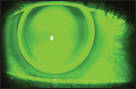

My patient was recently diagnosed with keratoconus and was referred to me for fitting. Her best refraction OD was –0.50 –4.00 x 005 to 20/80. The topography OD (Figure 1) showed a pretty typical nipple cone pattern with a small, central steep area within the pupil. This type of cornea can be fit with a smaller-diameter, traditional keratoconus design, and we chose to use the Rose K2 (Blanchard) design. Figure 2 shows the best-fitting lens from our diagnostic set, which had a 6.0mm base curve radius and an 8.7mm overall diameter.

Figure 1. Right eye topography.